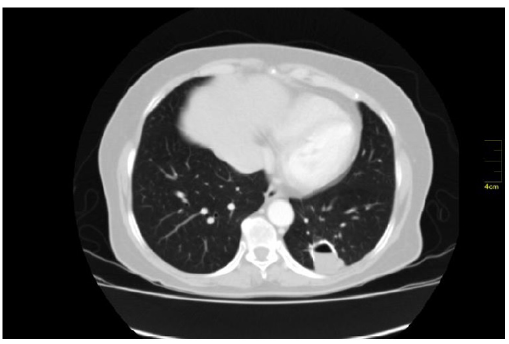

En la tomografía de tórax se observaba, en el lóbulo inferior izquierdo, una cavidad aérea de paredes calcificadas con niveles hidroaéreos en su interior, siendo sugestivo de una lesión cicatricial antigua. Ante los hallazgos poco sugestivos de malignidad se decide solicitar nueva tomografía de control en un año, en el que persiste la lesión cavitada en lóbulo inferior izquierdo, con bordes calcificados, con aparición de una lesión de densidad de tejidos blandos en su interior (figura 1).